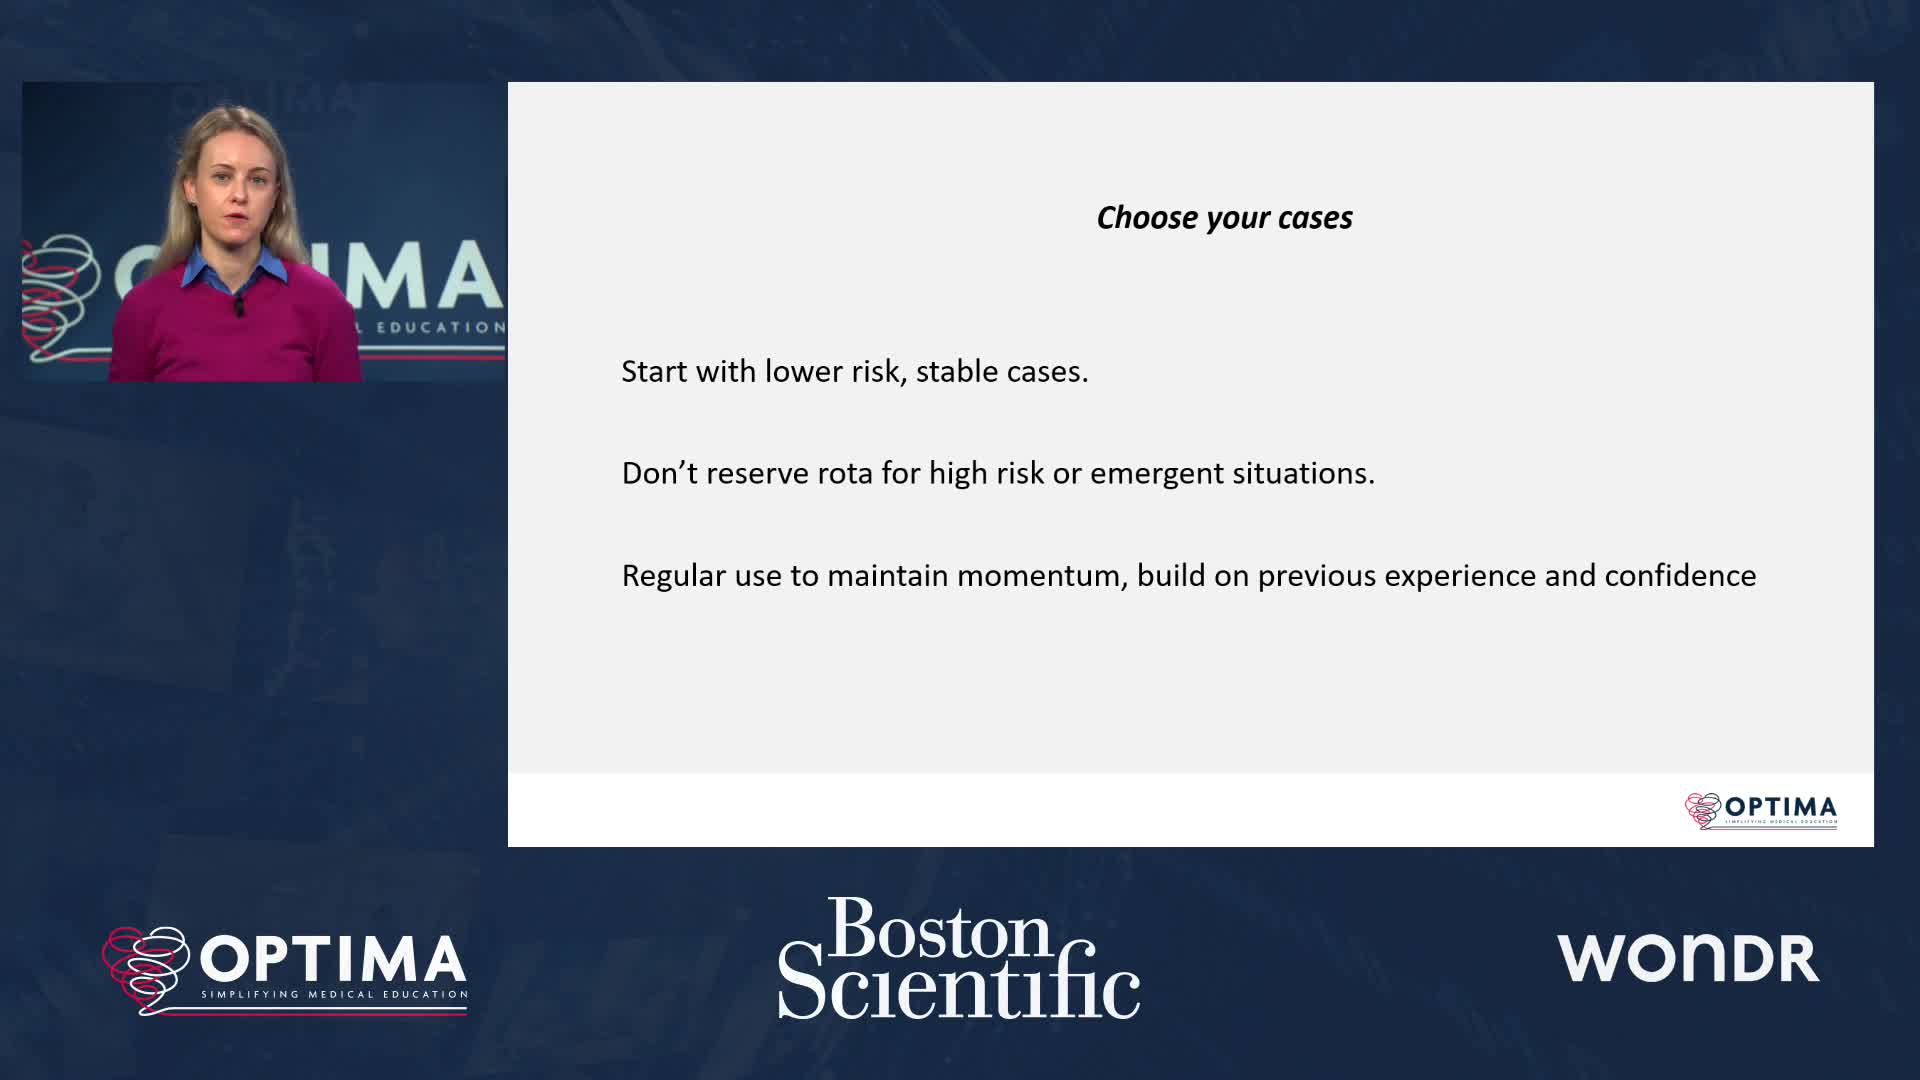

Calcium webinar with Boston Scientific

Treatment of coronary arterial calcium (CAC) has being redefined. We explore the interaction between CAC and patient...